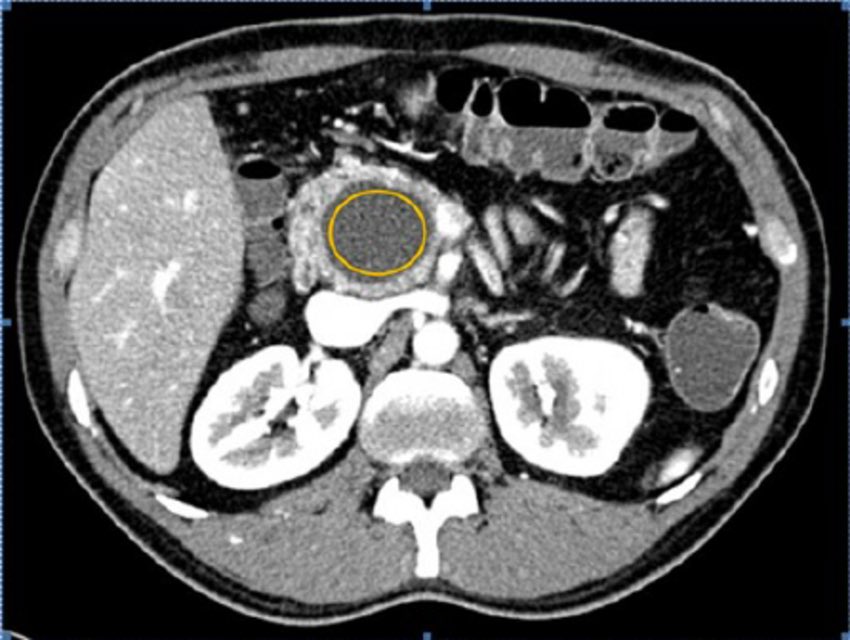

في معضم الأحيان يتم اكتشاف هذه الأكياس عن طريق الصدفة اثناء اجراء أشعة مقطعية، موجات صوتية، او رنين مغناطيسي لأي عرض اخر غير متعلق بالبنكرياس. و غالبا ما تكون بدون اعراض. فيما يكتشف البعض بسبب وجود اعراض غير واضحة مثل الألم. ينتج الجزء الآخر من الأكياس بعد التهاب الغدة.

٢. شكل الأكياس و حجمها

٣. مكونات الأكياس و نوع السائل و كثافته

٤. سبب تكون الأكياس و وجود اتصال بالقناة الرئيسة في الغدة

معظم اكياس البنكرياس هي حميدة بطبعها و غالبا لا تحتاج الى الإزالة. في حالات قليلة نوعا ما يتم ازالتها جراحيًا منعًا لاحتمالية تطورها الى أورام خبيثة مستقبلًا لا سمح الله. و تتم دراستها عادة باستخدام المنظار الصوتي و في خلال ١٥ الى ٣٠ دقيقة و بدون الحاجة الى تنويم بالمستشفى.